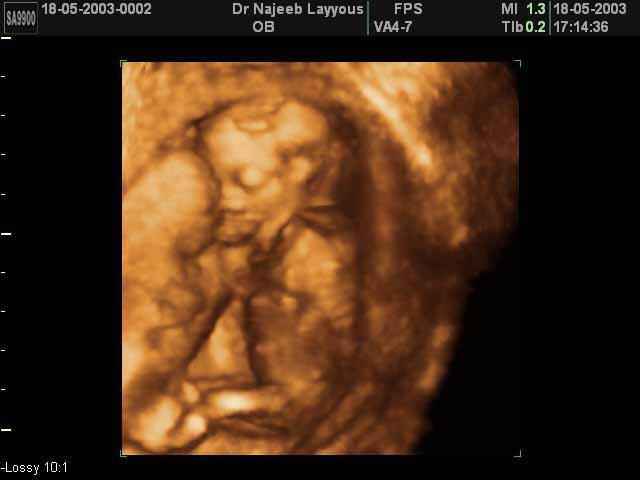

3D second trimestre échographie Photos de numérisation - deuxième partie de la grossesse | Dr N Layyous

3D second trimestre échographie Photos de numérisation - deuxième partie de la grossesse